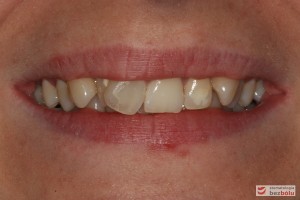

Pacjentka lat 26 zgłosiła się do gabinetu celem korekcji uśmiechu. Głównym zmartwieniem były problemy estetyczne, które znacznie wpływały na jakość życia pacjentki. Wykonano leczenie zachowawcze zębów oraz analizę cefalometryczną i analizę modeli diagnostycznych. Zaplanowano leczenie aktywne aparatem DAMON dla szczęki i żuchwy, które trwało 2 lata. Po fazie leczenia aktywnego rozpoczęto leczenie retencyjne z użyciem szyny tłoczonej dla szczęki i retainera stałego dla żuchwy.